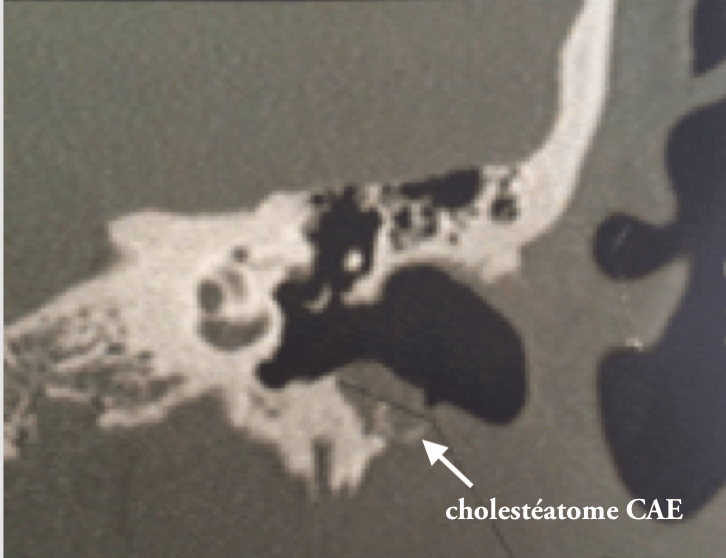

2/6 cholestéatome du CAE

Rare le cholestéatome du CAE, le tympan étant normal. Le diagnostic otoscopique est posé par la présence de squames et d'érosion osseuse. Ce sont des patients qui font des otites externes très rapprochées.